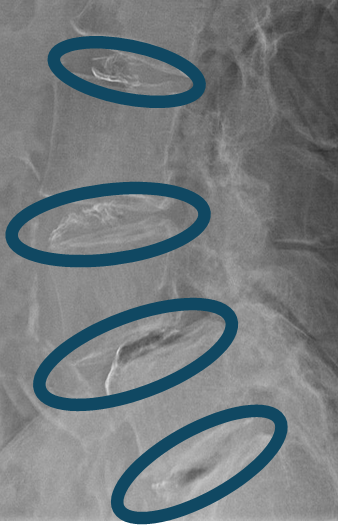

患者様と相談の元、L2/3,3/4,4/5,5/sにセルゲル法を施行

DiscoGelを入れた後の画像になります。

治療は 40分 程度で終了